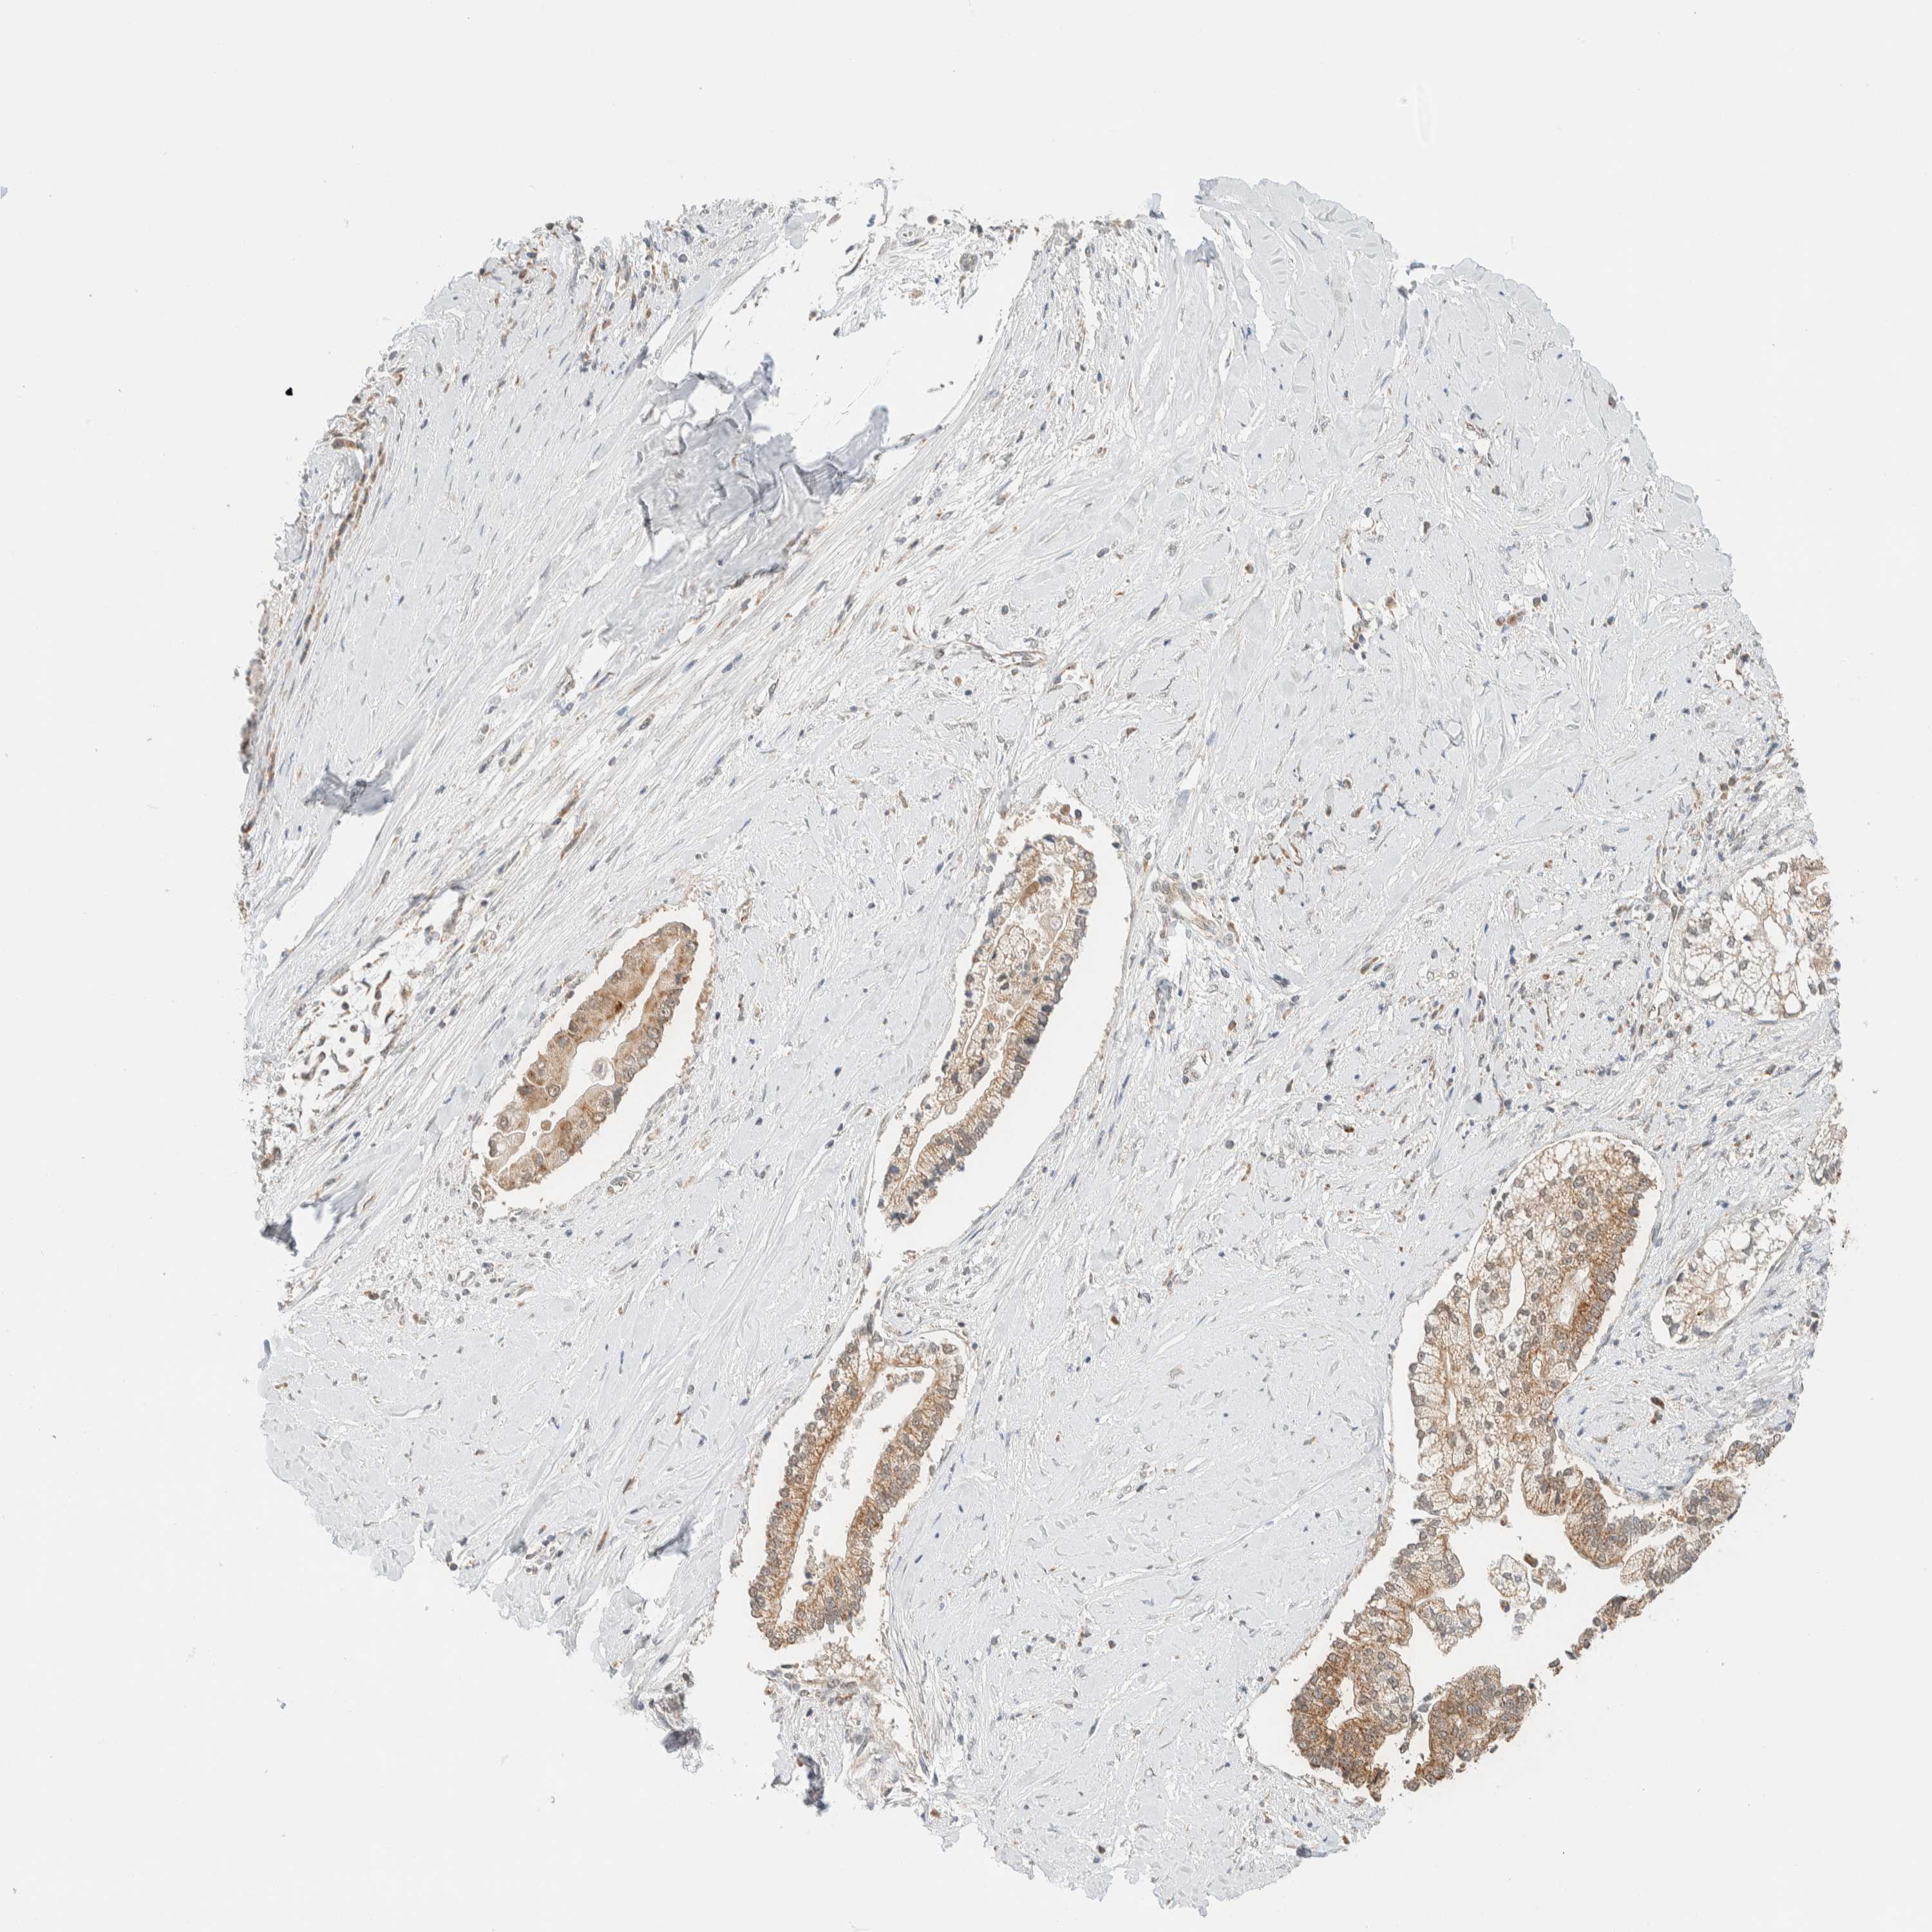

LIVER CANCER - Protein expressioni

A mouse-over function shows sample information and annotation data. Click on an image to view it in a full screen mode. Samples can be filtered based on level of antibody staining by selecting one or several of the following categories: high, medium, low and not detected. The assay and annotation is described here.

Note that samples used for immunohistochemistry by the Human Protein Atlas do not correspond to samples in the TCGA dataset.

Antibody stainingi

Antibody staining in the annotated cell types in the current human tissue is reported as not detected, low, medium, or high, based on conventional immunohistochemistry profiling in selected tissues. This score is based on the combination of the staining intensity and fraction of stained cells.

Each image is clickable and will lead to virtual microscopy that enables deeper exploration of all samples and also displays staining intensity scores, fraction scores and subcellular localization as well as patient and tissue information for each sample.

Antibody HPA024550

Antibody HPA027160

Staining

High

Medium

Low

Not detected

Intensity

Strong

Moderate

Weak

Negative

Quantity

>75%

75%-25%

<25%

None

Location

Nuclear

Cytoplasmic/membranous

Cytoplasmic/membranous,nuclear

Cholangiocarcinoma

Carcinoma, Hepatocellular, NOS